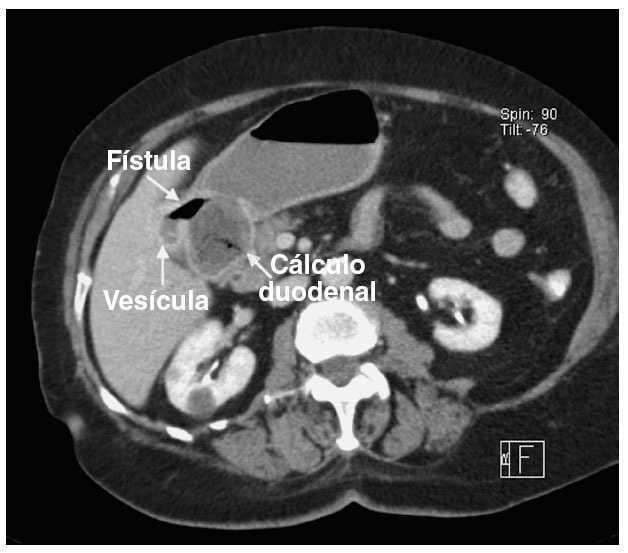

El síndrome de Bouveret es una enfermedad muy poco frecuente que afecta al aparato digestivo. Consiste en una obstrucción a nivel del estómago o el duodeno causada por un cálculo biliar de gran tamaño. El cálculo pasa al estómago o duodeno debido a la formación de una fístula colecistogastroduodenal, es decir una fístula que forma un trayecto anómalo que une la vesícula biliar con el estómago o el duodeno. El síndrome de Bouveret se considera la variedad menos frecuente de íleo biliar.[1] No debe confundirse este síndrome con la Taquicardia de reentrada del nódulo AV o enfermedad de Bouveret.

El diagnóstico de la afección es difícil debido a la escasa frecuencia del trastorno. Generalmente es necesario realizar técnicas de imagen como ecografía o resonancia magnética nuclear que descubran la situación anómala del cálculo y endoscopia digestiva.